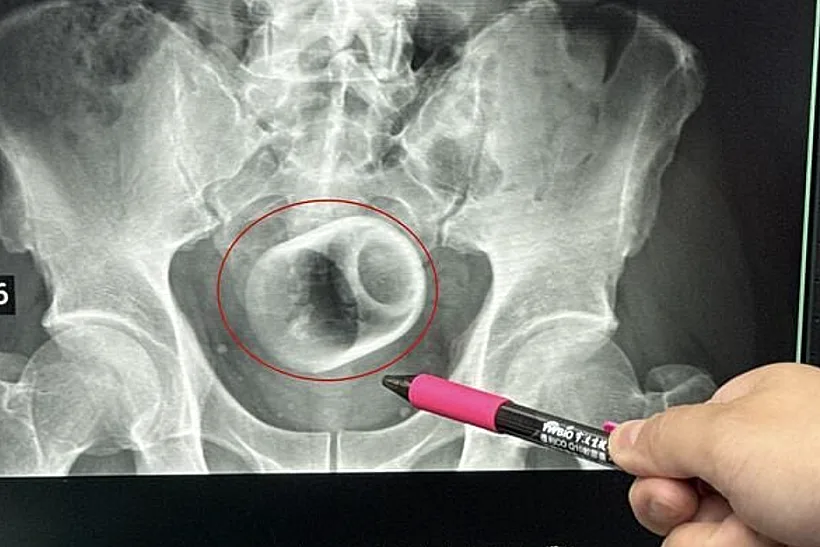

תושב טאיוואן בשנות ה-30 לחייו הגיע לפני מספר ימים לבית חולים בעיר טאיצ'ונג לאחר שסבל מעצירות קשה במשך שלושה ימים. הוא ציפה לקבל טיפול רגיל, אך צילום הרנטגן חשף משהו שהפתיע את הצוות הרפואי – כוס קרמיקה באורך 8 ס"מ שנמצאה תקועה עמוק בפי הטבעת שלו.

הרופאים ניסו תחילה להוציא את הכוס בעזרת כלים רפואיים, אך המשטח החלק של הקרמיקה הפך את המשימה לבלתי אפשרית. בסופו של דבר, לא הייתה ברירה אלא לבצע ניתוח חירום בחלל הבטן כדי להוציא את הכלי בצורה בטוחה.